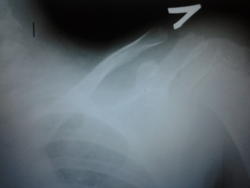

девочка 7лет от хирурга с жалобами на наличие болезненного образования в ключице. Хирург пишет:больна около года, об-но: в области грудин конца ключицы округлое образование болезненное при пальпации. Ds: Энхондрома. рекомендует рентген.

Хотелось бы для сравнения другую ключицу. Кажется нормальное строение.

а почему акцент сделан на акромиальный конец ключицы, такто тоже ничего плохого не вижу. а грудной конец плохо видно

меня смутила тонкая полоска уплотнения в акромиальном конце ключицы, по садофьевой срвнивала, чётко разница не определяется? Может и правда норма. А в грудном тоже не вижу, мягкий снимок.

Это может быть остеохондропатией грудинного конца ключицы (болезнь Фридриха). У нас несколько таких детей было.

Снимок ключицы в аксиальной проекции дал бы более детальную описательную картину. На представленном снимке патологии не видно.